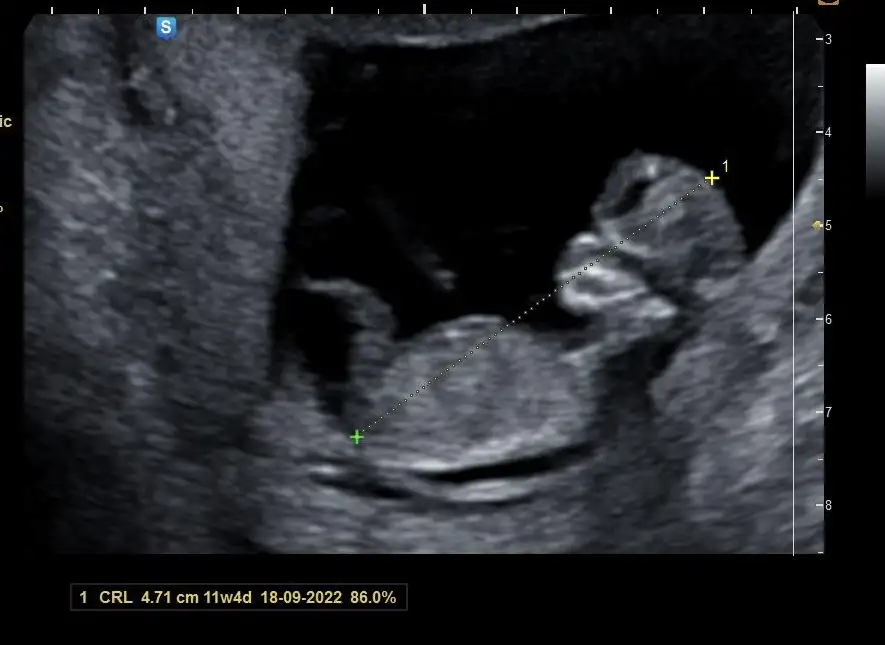

Şimdi doktordan geldim. Ne kadar büyümüş ya parmaklarına kadar sayılıyordu aşırı hareketli doktor zor ölçtü ensesini falan . Doktorum erkeğe benziyor ama yinede belli olmaz dedi fetal dna çıkar 10-15 güne ordan kesin öğreniriz zaten dedi. 11+3üz bugün uyumlu gidiyor hiçbir belirtim sıkıntım olmayınca korkuyordum ama görünce içim rahatladım. Tüp bebek ilaçlarınıda bıraktık sonunda şükür iğne ve fitili.

• AEED2E6D-7296-4E66-B702-6AE0C99A10DD.webp

19,8 KB · Görüntüleme: 108